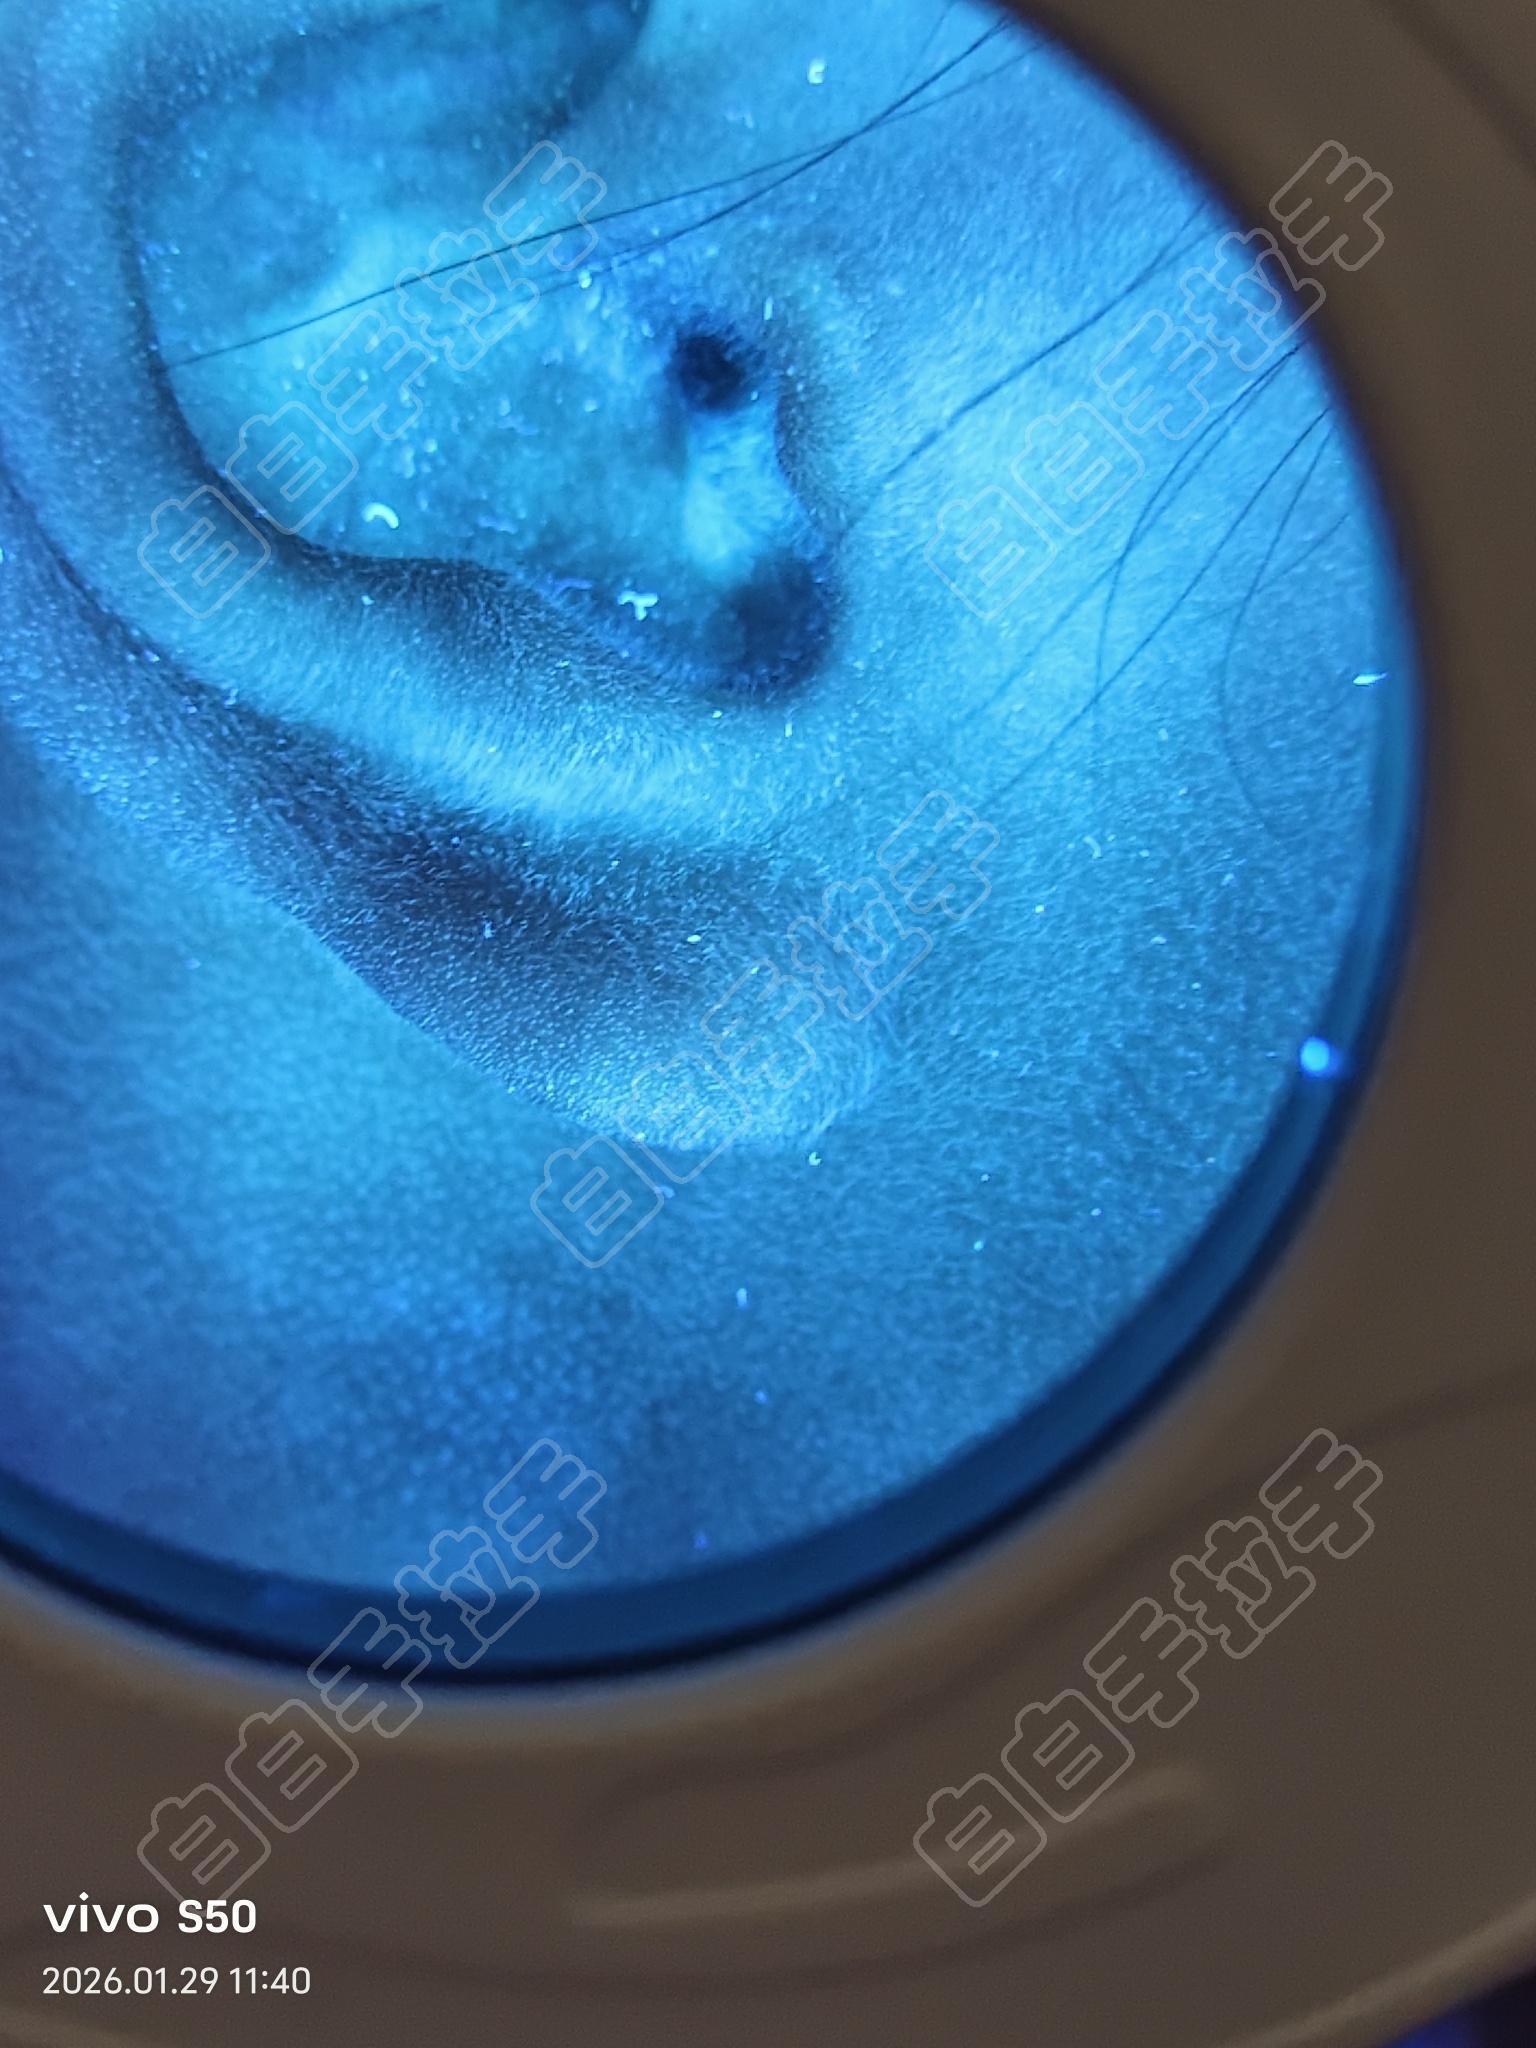

请教,耳蜗里面怎么照光?

有什么注意事项,怎么照光,小孩十岁,医生说可以自己在家照光,这个部位是不是不好恢复

这个位置不好弄

先用棉签涂一点他克司莫软膏  再找个吸管或者纸把它剪出来,去照一下光,耳朵其实很容易恢复

耳洞里面照不了